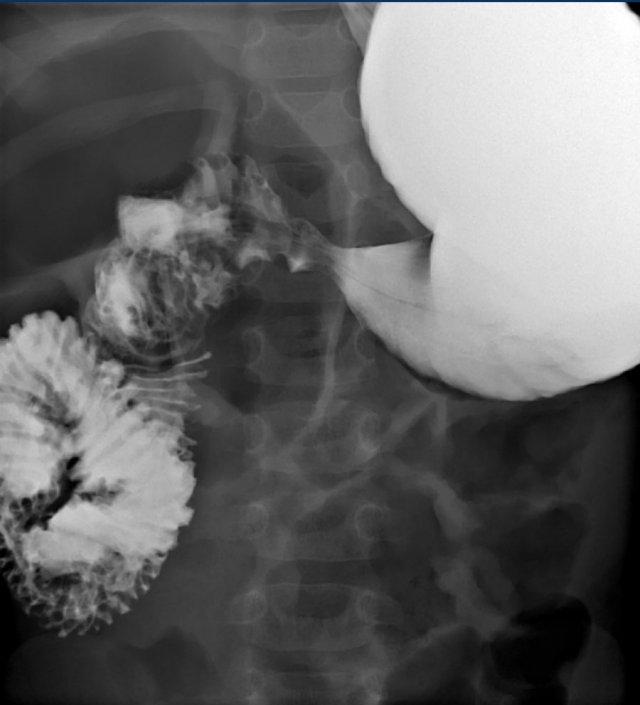

Các dấu hiệu bao gồm:

- Tá tràng đoạn gần giãn rộng (dấu hoa thị)

- Một lượng nhỏ thuốc cản quang đi qua màng ngăn tá tràng đến tá tràng đoạn xa (mũi tên)